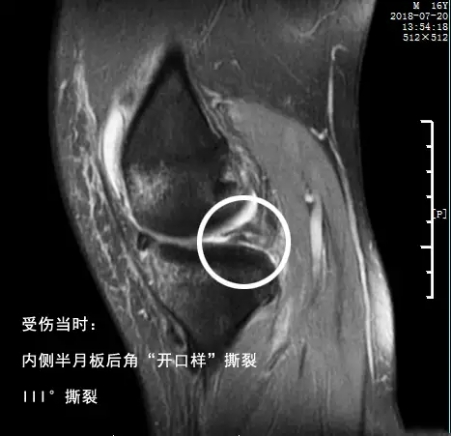

第三,半月板影像。接下来提示外侧半月板后角斑片状高信号影,达关节面边缘;前角内见线性高信号影(未提及达关节面说明没有)。这里说的半月板后角达关节面边缘,就说明外侧半月板是III°撕裂,核磁影像一般是这样的:

或者是这样的:

大家可以看到半月板已经完全有一部分离家出走,损伤肯定突破了其上下表面,并且导致了关节内的大量积液。而镜下很可能是这样子的: